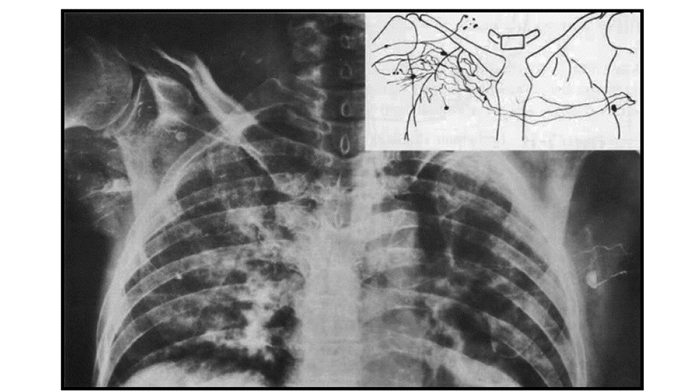

• 摘要: 淋巴水肿是近年来康复医学领域广泛关注的热点问题, 以手法淋巴引流(manual lymphatic drainage, MLD)为关键技术的淋巴水肿综合消肿治疗正在全国各地迅速开展。本文报道1例由一侧乳腺癌根治手术诱发对侧躯干和上肢原发性淋巴水肿加重的罕见病例, 患者通过MLD治疗获得缓解。通过回顾本病例诊治过程, 可加深对淋巴水肿发病机制复杂性的认识, 并为临床个体化诊疗提供借鉴。

Abstract: Lymphedema is a hot issue that has attracted wide attention in the field of rehabilitation medicine in recent years. The complex decongestive therapy of lymphedema including manual lymphatic drainage(MLD) as the key technology is developing rapidly all over the country.We report a rare case of aggravated primary lymphedema in the contralateral limb and trunk after radical mastectomy. The patient achieved remission through MLD treatment. By reviewing the diagnosis and treatment of this case, we can deepen the understanding of the complexity of the pathogenesis of lymphedema and provide reference for individualized diagnosis and treatment of lymphedema.